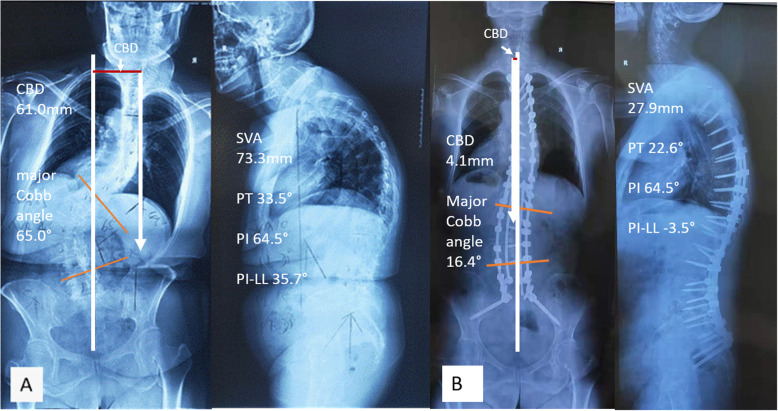

Full-spine standing posteroanterior and lateral radiographs were analyzed preoperatively and post-op 2 weeks or at hospital discharge (Fig. 4a, b). The measurements were done using Surgimap (version 2.2.15; Spine Software, New York, NY) by two independent researchers and the mean values were collected for analysis. The following parameters were measured on the coronal plane: (1) coronal balance distance (CBD), defined as the horizontal distance between the C7 plumb line (C7 PL) and CSVL, C7 PL shifted to the right was defined as positive, and to the left as negative; (2) major Cobb angle. Right curve was defined as positive, left curve as negative; (3) the correction in CBD was defined as ΔCBD, ΔCBD = preoperative CBD- postoperative CBD; (4) the correction in major Cobb angle was defined as Δ major Cobb angle, Δ major Cobb angle = preoperative major Cobb angle- postoperative major Cobb angle. Sagittal parameters included: (1) thoracic kyphosis (TK), the angle between the inferior endplate of T5 and T12, kyphosis was defined as positive, and lordosis as negative; (2) pelvic tilt (PT), a pelvic positional parameter; (3) pelvic incidence minus lumbar lordosis, (PI-LL); (4) sagittal vertical axis (SVA), the distance between C7 PL and posterosuperior corner of S1. (5) corrections in sagittal parameters such as Δ thoracic kyphosis, Δ PT, Δ PI-LL, and Δ SVA, they were defined in the same way as corrections in coronal parameters.

Preoperatively, there were no significant differences regarding CBD, major Cobb angle and imbalance/balance ratio between IGCA and non-IGCA groups (Table 2). After surgery, the CBD in IGCA group was significantly improved from 24.7 ± 20.3 mm preoperatively to 12.6 ± 6.4 mm postoperatively (t = 3.185, p = 0.004), and the imbalance/balance ratio was reduced significantly from 55.6% (15/27) preoperatively to 11.1% (3/27) postoperatively (χ2 = 12.000, p = 0.001). On the contrary, the CBD in non-IGCA group was not improved (17.4 ± 15.1 vs. 18.3 ± 11.4, t = 0.327 p = 0.747)), and the imbalance/balance ratio frustratingly increased from 32% (8/25) preoperatively to 48% (12/25) postoperatively (χ2 = 1.333, p = 0.248). Compared to the non-IGCA group, the amount of correction in CBD (CBD) was significantly larger in the IGCA group (t = 3.274, P = 0.002), and the imbalance/balance ratio in IGCA group was significantly lowered (χ2 = 8.606 p = 0.003) (Table 2). The major Cobb angle in addition to sagittal parameters (SVA, TK, PT, PI-LL) and their changes exhibited no significant differences between IGCA and non-IGCA groups (Tables 2, 3).